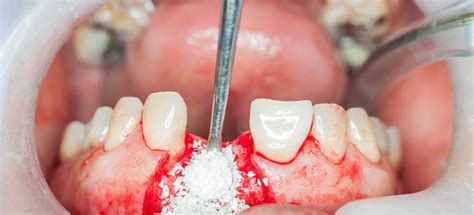

Regeneración Ósea Guiada (ROG)

Es una técnica que emplea biomateriales junto con una membrana para formar una barrera que impida que otros tejidos no óseos invadan el área del injerto. Esto permite que el hueso nuevo se forme sin interferencias, ayudando a reconstruir las áreas afectadas.